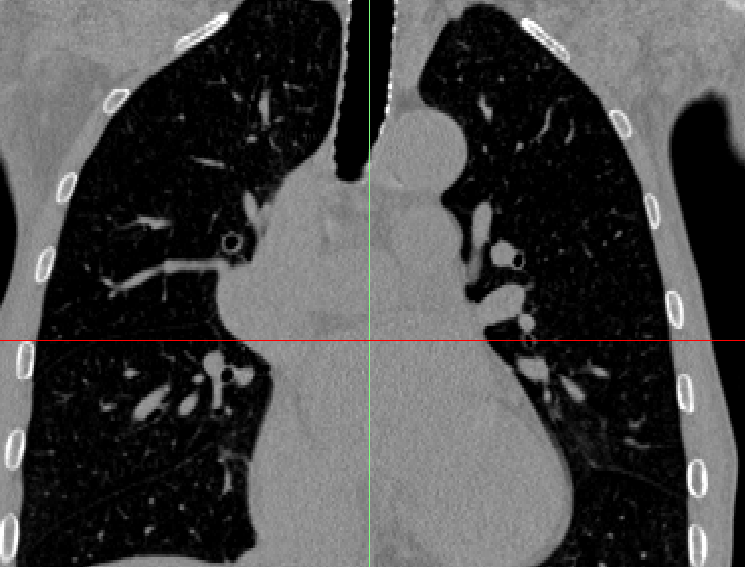

就诊患者:女性,70岁,由于出现右侧腹部胀痛不适,伴恶心呕吐食欲不振,消瘦乏力等症状到医院就诊。确诊为胆管细胞癌,继发胆管扩张,下腔静脉受侵可能。

案例通过3D重构从任意角度显示了肝脏病灶的位置及其与周围血管的空间毗邻关系,将立体肝脏及肝内管道系统的走行一并呈现。